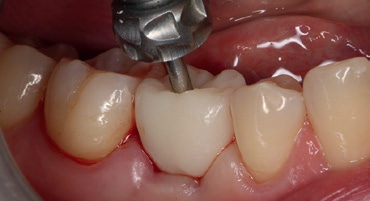

Nach der geführten Implantatbettaufbereitung wurde das Astra Tech Implant System EV 4,8C × 13 mm durch die Hülse hindurch mit Höhenanschlag in seine geplante Position inseriert (Eindrehmoment final: 45 Ncm) (Abb. 8 bis 10). Die Lage des Implantats wurde mit einer intraoralen Röntgenaufnahme postoperativ überprüft (Abb. 11). Es folgte die digitale Abformung mit der CEREC Omnicam: Um die Implantatposition exakt zu übertragen, wurde ein Scanbody platziert (Abb. 12). Der dabei erzeugte Scan wurde für das präzise Design eines Provisoriums mit der Abformung des Milchzahnes überlagert und im Anschluss gefräst (Abb. 13). Das Kunststoffprovisorium wurde mit der dazugehörigen TiBase verklebt (Multilink Hybrid Abutment, Ivoclar Vivadent). Zuvor wurden sowohl die TiBase als auch das Zirkonabutment sandgestrahlt, im Ultraschallbad gereinigt und im Anschluss silanisiert (Monobond plus, Ivoclar Vivadent). Im nächsten Schritt wurde das Provisorium mit dem Implantat okklusal verschraubt (Abb. 14) und mit Komposit verschlossen (Abb. 15 bis 17). Um eine Überbelastung des Implantats während der Einheilzeit zu vermeiden, war eine Nonokklusion von 0,5 bis 1 mm zum Antagonisten zu beachten. Dazu gehörte auch die Empfehlung an die Patientin, das Provisorium in den ersten Monaten nur eingeschränkt zu belasten (weiche Kost).